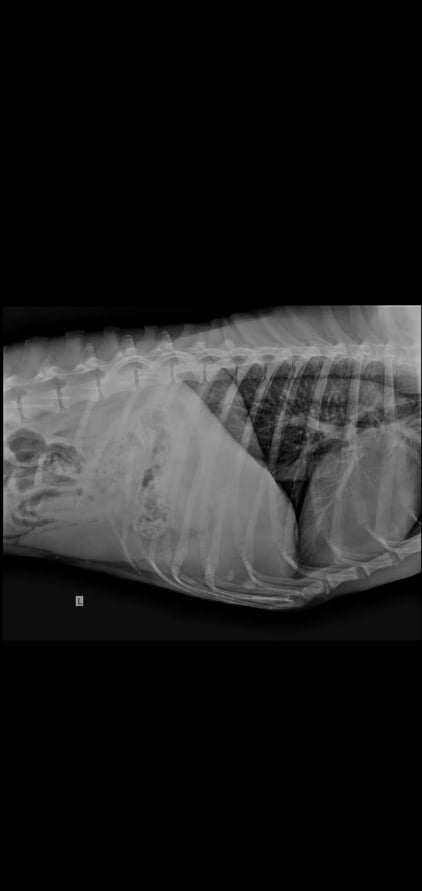

Sancho hat eine alte Verletzung, die ihn jedoch nicht beeinträchtigt: Alte Rippenbrüche… wie dies passiert ist, ist unbekannt.